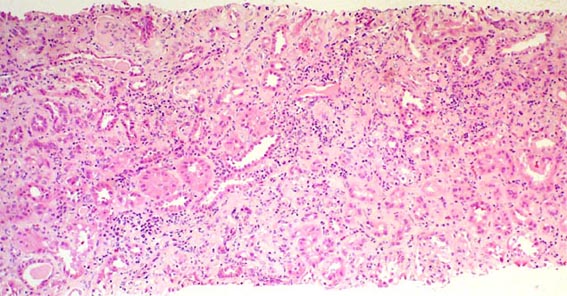

Figure 1.

H&E, X100.